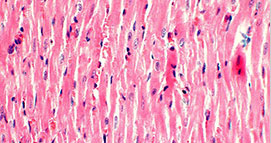

5、HE染色

蘇木精(Hematoxylin)和伊紅(曙紅����,Eosin)染色法是組織學(xué)標(biāo)本及病理切片標(biāo)本的常規(guī)染色,簡(jiǎn)稱HE染色��。經(jīng)HE染色后��,細(xì)胞核被蘇木精染成紫藍(lán)色����,多數(shù)細(xì)胞質(zhì)及非細(xì)胞成分被伊紅染成粉紅色���。